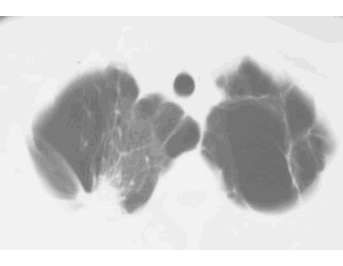

SHAPE - irregular

MARGIN - spiculated

SIZE - 4 cm

DENSITY - can't tell on these CT windows (lung windows)

NOTE: any lung opacity that is over 3 cm in diameter or spiculated in shape must be called a 'MASS'